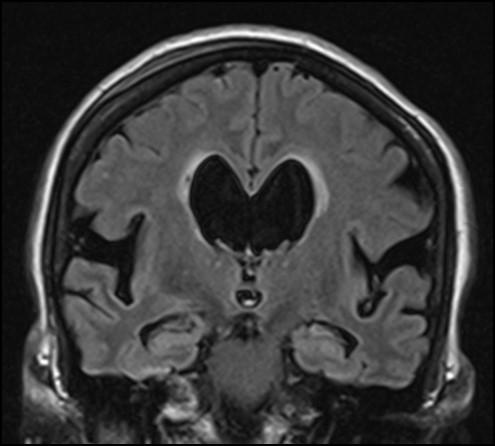

image: Idiopathic normal pressure hydrocephalus is characterized by enlarged ventricles of the brain and obliterated parasagittal sulci.

In iNPH, the circulation of cerebrospinal fluid (CSF) is disturbed for an unknown reason, leading to a slightly elevated brain pressure and dilation of the brain ventricles. Symptoms of NPH include gait deviations, impaired short-term memory and urinary incontinence. Patients with iNPH often have changes in brain that are related to Alzheimer's disease.